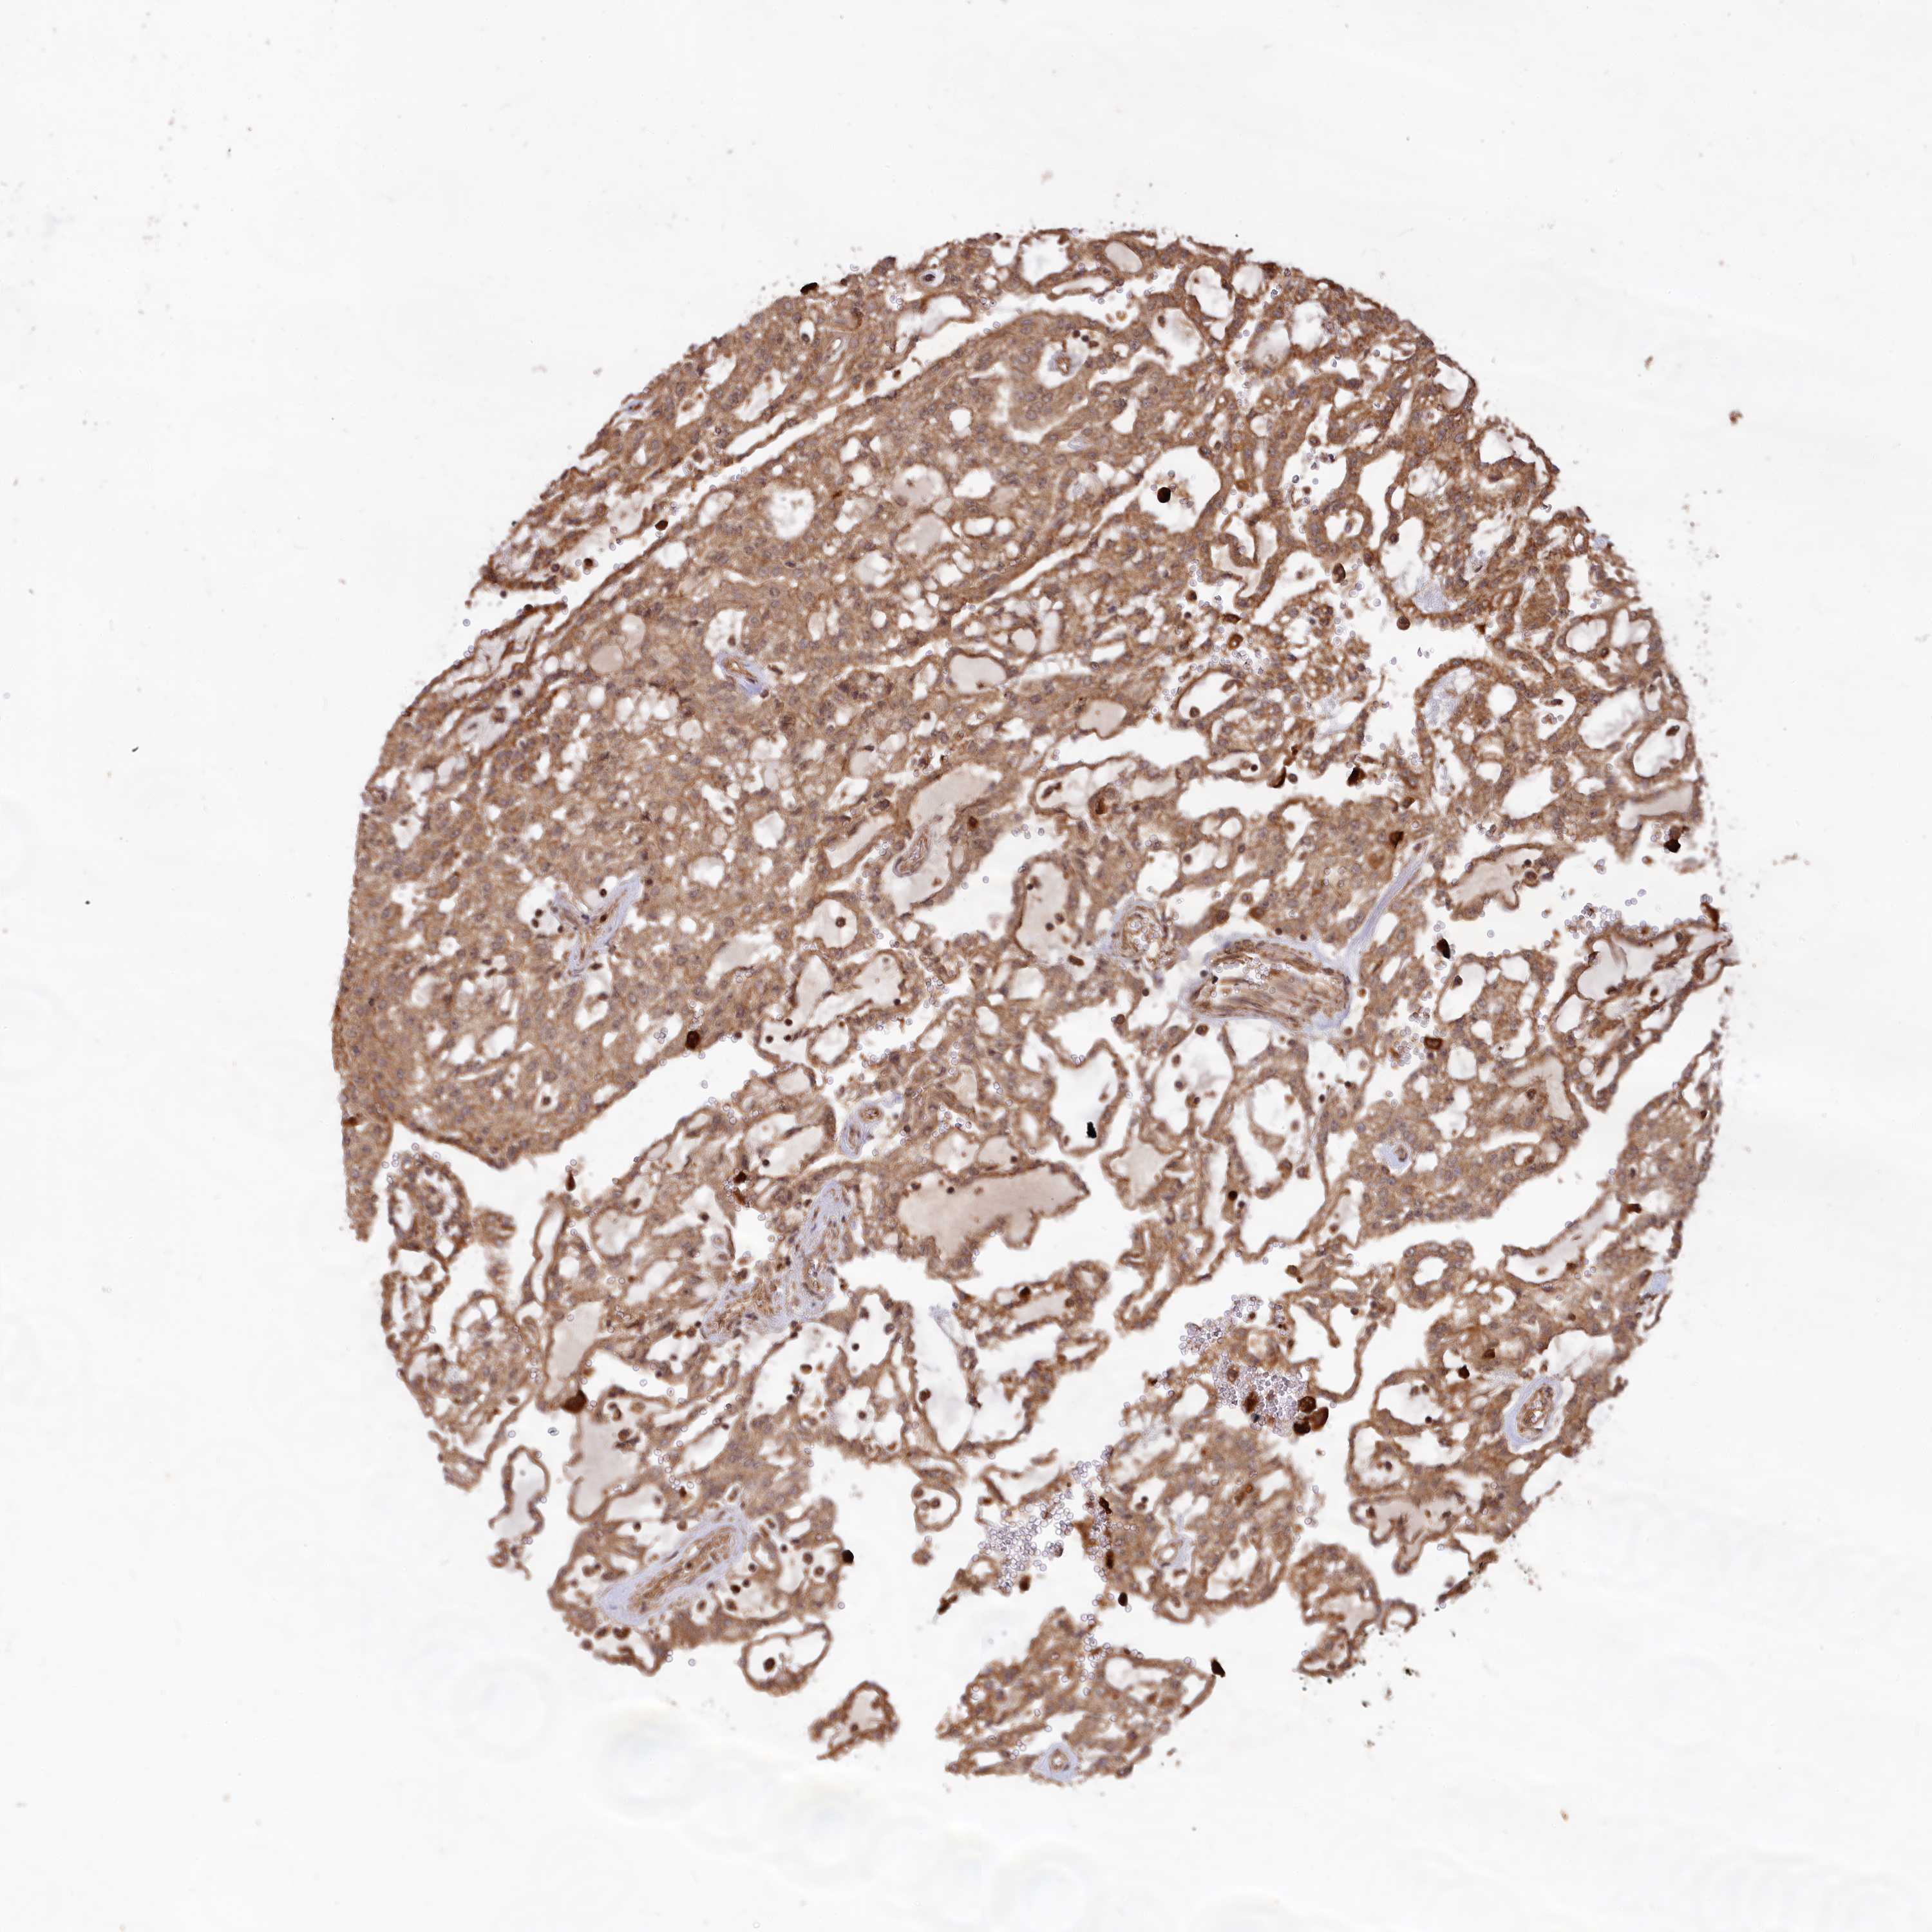

KIDNEY RENAL CLEAR CELL CARCINOMA (VALIDATION) - Interactive survival scatter ploti

The Survival Scatter plot shows the clinical status (i.e. dead or alive) for all individuals in the patient cohort, based on the same data that underlies the corresponding Kaplan-Meier plots. Patients that are alive at last time for follow-up are shown in blue and patients who have died during the study are shown in red.

The x-axis shows the expression levels (FPKM) of the investigated gene in the tumor tissue at the time of diagnosis. The y-axis shows the follow-up time after diagnosis (years). Both axes are complimented with kernel density curves demonstrating the data density over the axes. The top density plot shows the expression levels (FPKM) distribution among dead (red) and alive patients (blue). The right density plot shows the data density of the survived years of dead patients with high and low expression levels respectively, stratified using the cutoff indicated by the vertical dashed line through the Survival Scatter plot. This cutoff is automatically defined based on the FPKM cutoff that minimizes the p-score. The cutoff can be changed by dragging the vertical line or by entering a cutoff value in the square labeled "Current cut-off".

Under the Survival Scatter plot the p-score landscape (black curve; left axis) is shown together with dead median separation (red curve; right axis). Dead median separation is the difference in median mRNA expression between patients who have died with high and low expression, respectively. It is calculated as follows: median FPKM expression of dead patients with high expression - median FPKM expression of dead patients with low expression. This is intended to aid the user in visually exploring custom cutoffs and the associated p-scores and dead median separation.

Individual patient data is displayed and can be filtered by clicking on one or more of the category buttons on the top of the page. Categories describing expression level and patient information include: high, low, alive, dead, female, male and tumor stages. The scale of the x-axis can be toggled between linear and log-scale by clicking on the "x log" button. Mouse-over function shows TCGA ID, patient information and mRNA expression (FPKM) for each patient.

& Survival analysisi

Kaplan-Meier plots summarize results from analysis of correlation between mRNA expression level and patient survival. Patients were divided based on level of expression into one of the two groups "low" (under cut off) or "high" (over cut off). X-axis shows time for survival (years) and y-axis shows the probability of survival, where 1.0 corresponds to 100 percent.

CCDC174 is not prognostic in Kidney Renal Clear Cell Carcinoma (validation)

: 8.78

Average pTPM 8.2

Number of samples 100